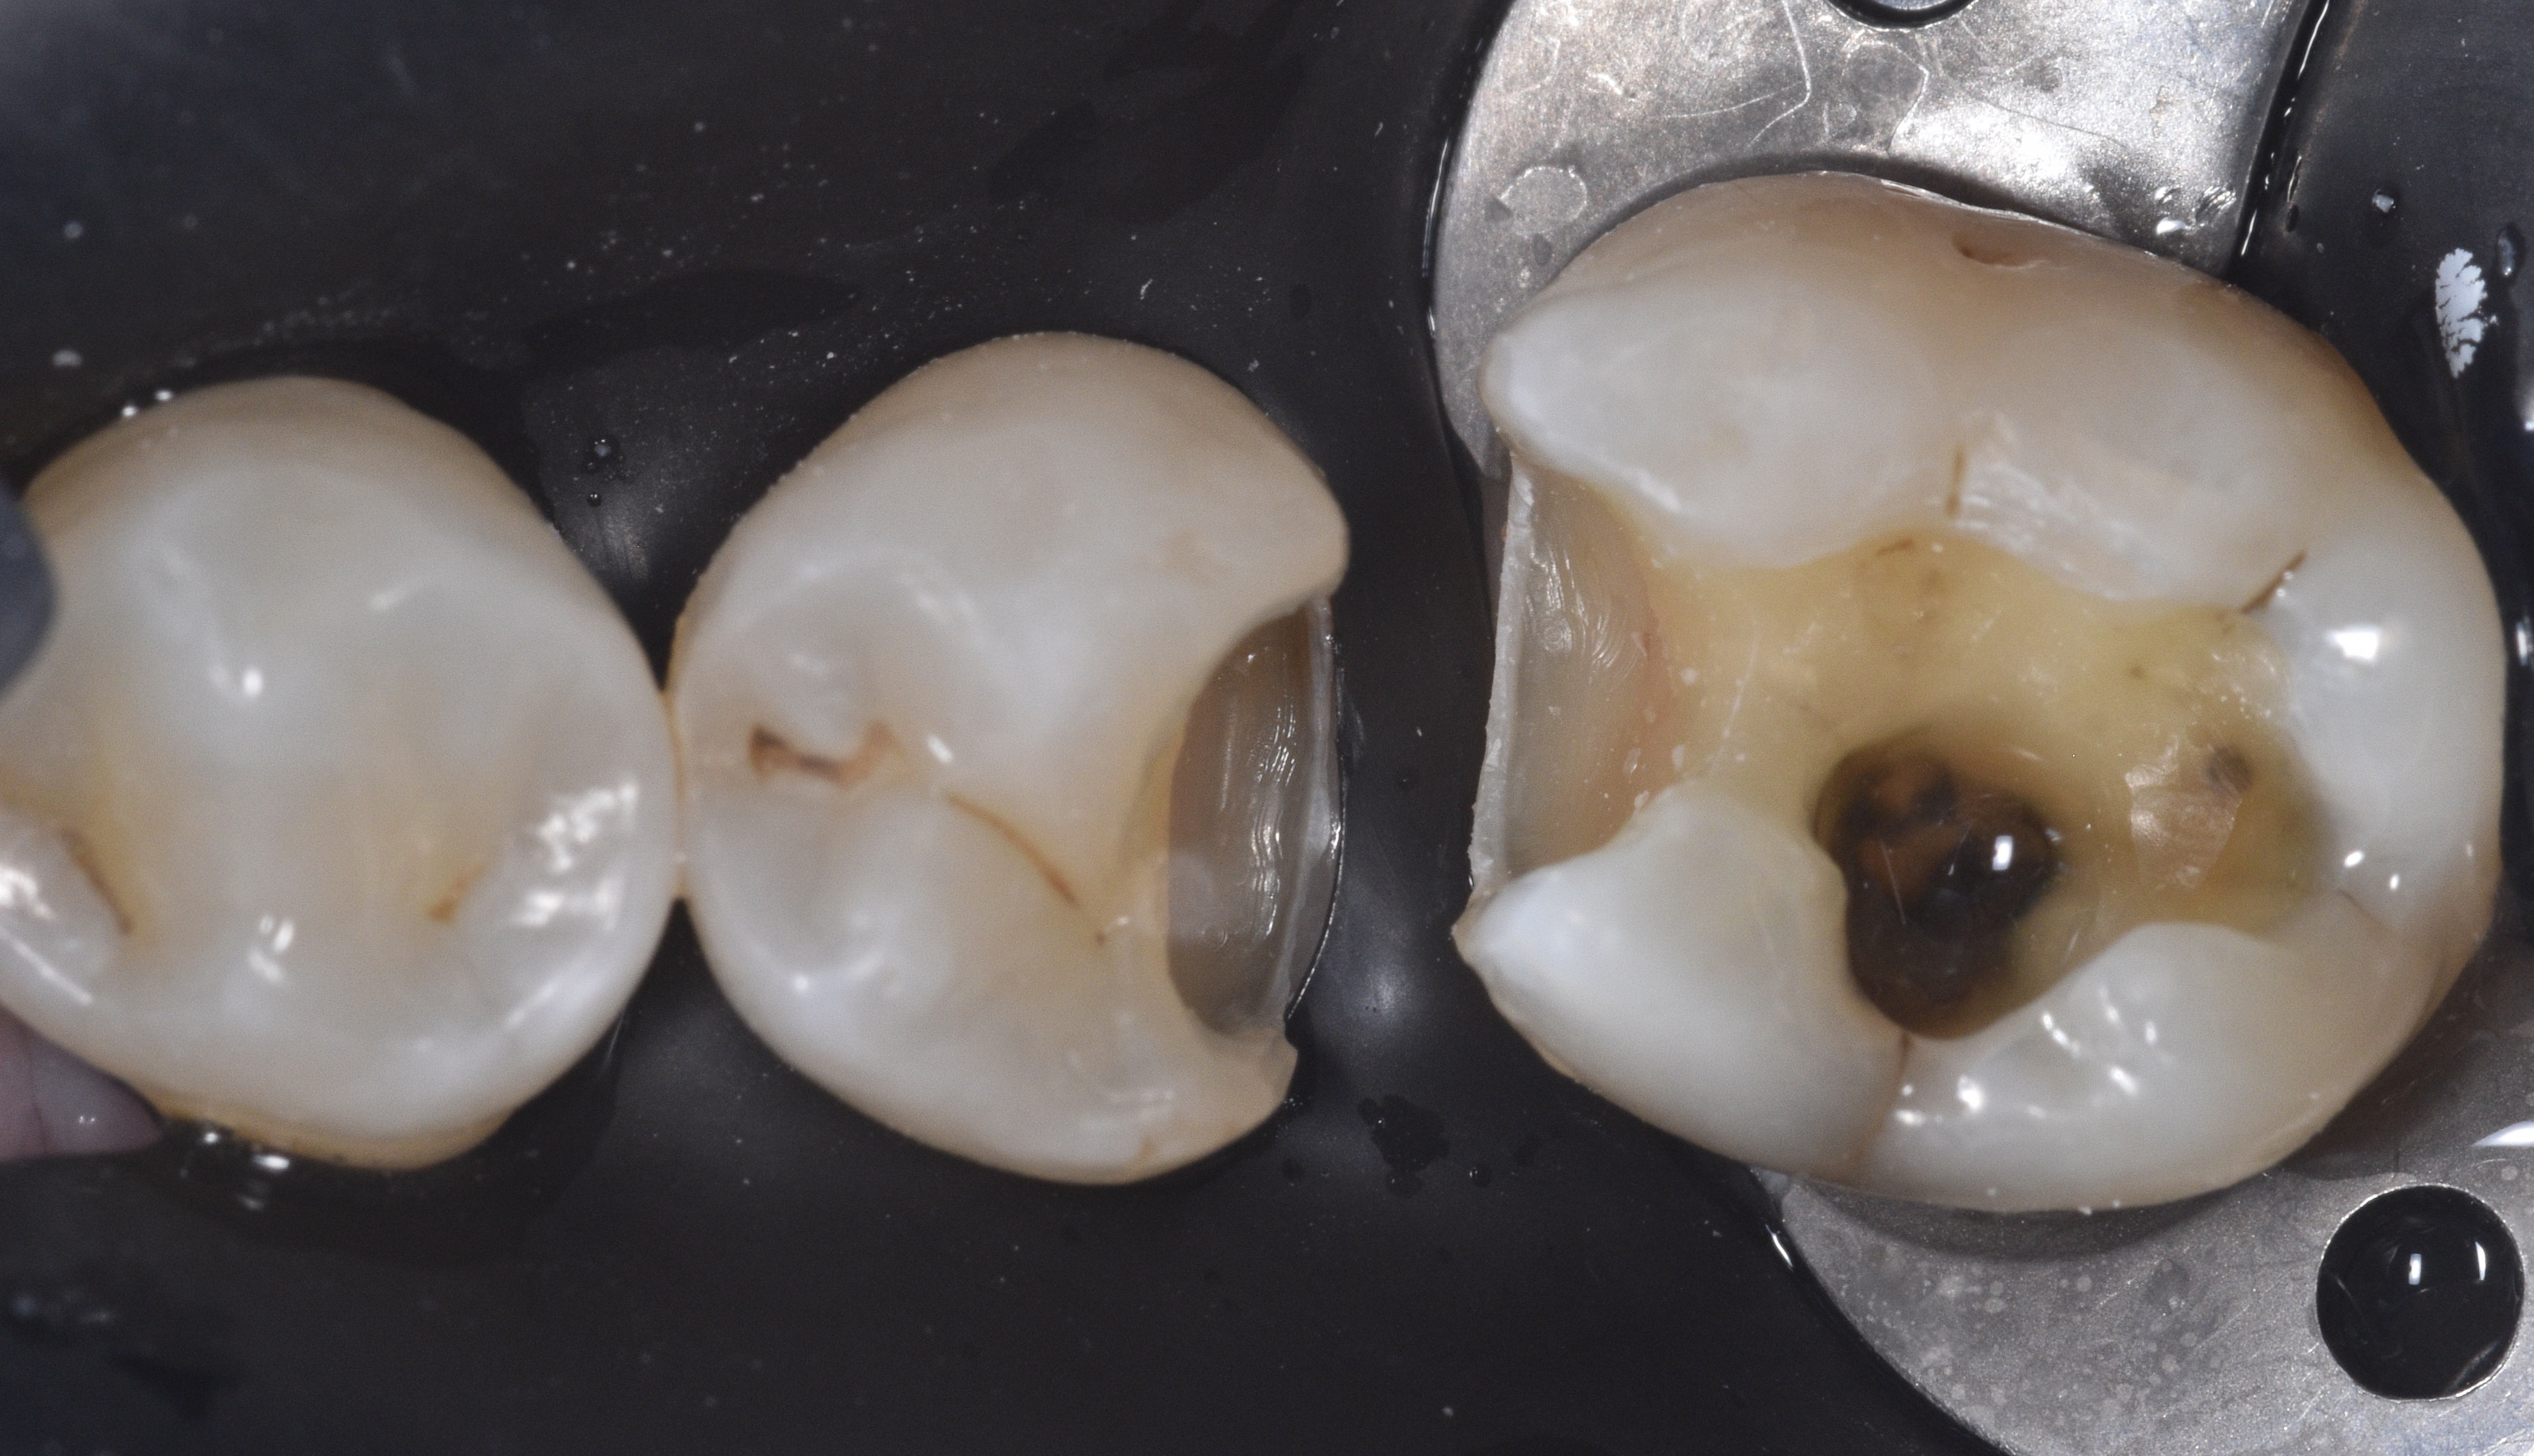

A 51-year-old man in good health came to my office with large carious lesions between teeth #29 (DO) and #30 (MO). As seen in the pre-op photo (Figure 1), this case was challenging because both teeth were rotated: tooth #29 was rotated toward the lingual and #30 toward the buccal, creating wide embrasures and a relatively small contact area.

Figure 1. Patient presented with large carious lesions between teeth #29 (DO) and #30 (MO).

After ensuring profound anesthesia with two carpules of OraBloc Articaine 4% containing epinephrine 1:100,000 administered via an inferior alveolar nerve block (IANB), rubber dam isolation was established to maintain a clean and dry working field. Access to the carious lesions was achieved using a #2 round diamond bur. As observed in Figure 2, the enamel exhibited areas of demineralization, and there was dark, infected dentin extending beyond the dentinoenamel junction (DEJ). Caries detection dye was employed to guide the excavation until all carious tissue was removed and a sound peripheral seal zone was obtained.

Figure 2. The enamel exhibited areas of demineralization, and infected dentin extending beyond the dentin enamel junction (DEJ).